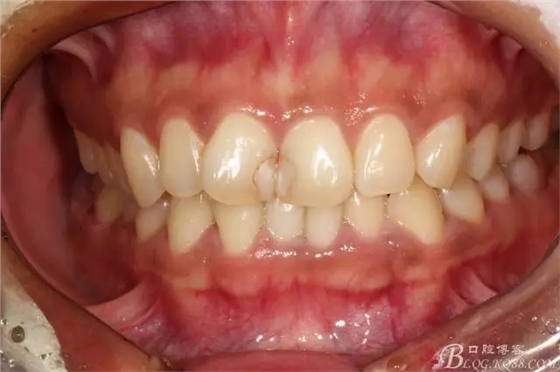

半年后(2016.9)復(fù)查照(這次復(fù)查已完全適應(yīng)修復(fù)后的效果,冷熱也不敏感了,我的心也就放下了)

患者還是比較信任,希望能追蹤更長期的效果。